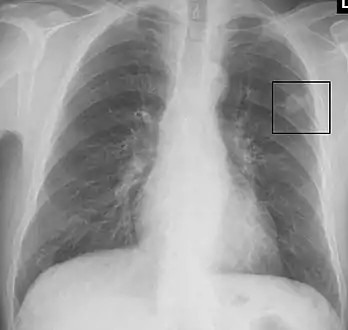

Chest X-ray showing lung cancer in the left lung

Most cancers are initially recognized either because of the appearance of symptoms or through screening. A physicians gut feeling may also be useful in picking up the disease.[104] Neither of these leads to a definitive diagnosis, which requires the examination of a tissue sample by a pathologist. People with suspected cancer are investigated with medical tests. These commonly include blood tests, X-rays, (contrast) CT scans and endoscopy.